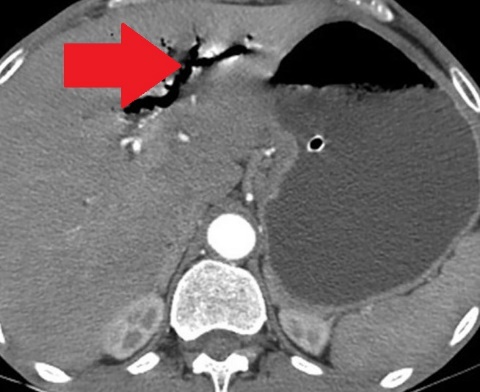

Contrast-enhanced CT of the abdomen, revealing air in intrahepatic biliary tree (pneumobilia) (red arrow)